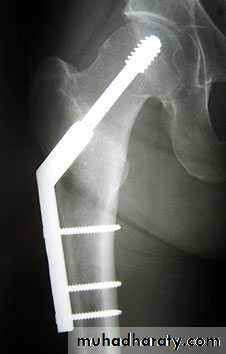

4.DHS.

1.Sliding nail

Lower limbs

2.L-plate